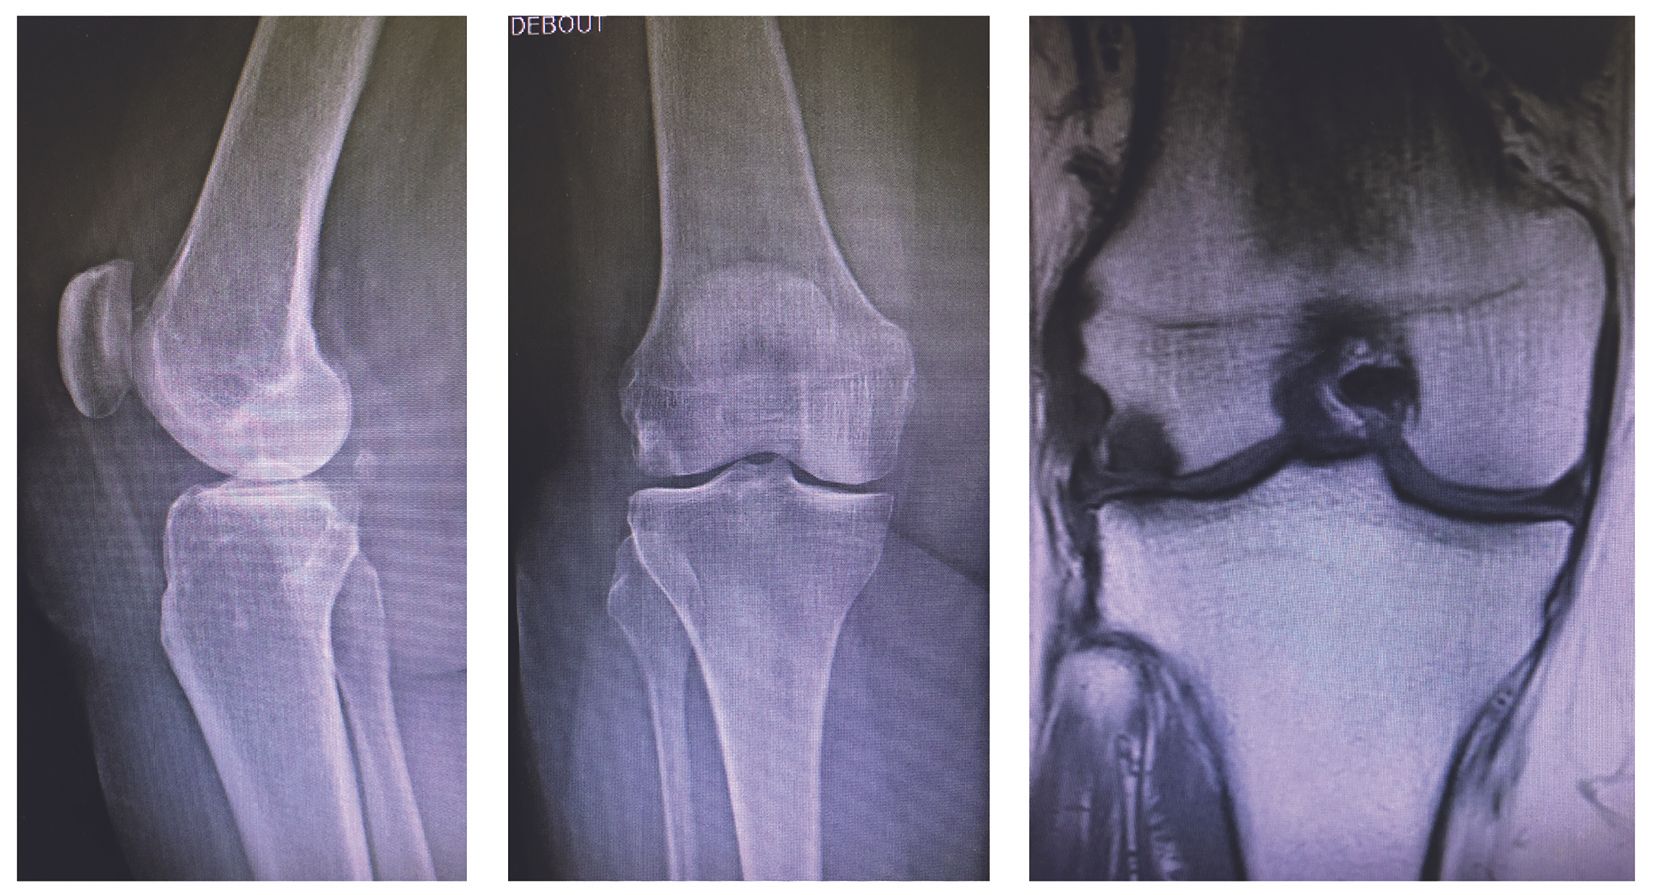

Isolated damage to the lateral tibiofemoral compartment is a determining factor for the indication (Fig. 1). Although usually due to osteoarthritis, damage caused by very localized necrosis of the lateral condyle is also a good indication (Fig. 2). The preoperative deformity should be only moderate, preferably intra articular or epiphyseal, and reducible on stress x-rays.

In the sagittal plane, careful assessment is again required to ensure the anterior cruciate ligament (ACL) is intact; an anterior drawer sign greater than 10mm or a soft endpoint in the Lachmann test are typically contraindications to UKA. ACL tears and anterior translation of tibia can in fact lead to loosening (rocking chair effect) and early wear of the prosthetic lateral tibial plateau.

The average time to surgical revision was 5.1 years. Two hundred and twenty-nine implants were still in place without the need for further intervention by the time of last follow-up (Group R0). The average IKS knee score was 87.0 ± 10.9 (45–100), and the IKS functional score was 80.2 ± 14.3 (30–100). Average maximum flexion was 125 ± 11° (85–140). As regards overall patient satisfaction, 94.3% of patients were ‘very satisfied’ or ‘satisfied’. The leading cause of revision was progression of osteoarthritis in other compartments of the knee (26 cases), followed by tibial loosening (4 cases), then misalignment/impingement (3 cases), sepsis (3 cases), unexplained pain and stiffness (2 cases) and medial necrosis (1 case). To assess the implant effect, we compared the ‘resurfacing implant’ group (n=91, 34.0%) represented by a single type of implant (HLS Uni Evolution, Tornier®) to the ‘cutting implant’ group (n=177, 66.0%) comprising the four other types of implant (Alpina Uni®, Biomet; ZUK®, Zimmer; Sigma HP®, DePuy Synthes; Uni Score®, Amplitude). There was no statistically significant difference in terms of revision-free survival, with 84.6% (77 implants) in the resurfacing implant group and 85.9% (152 implants) in the cutting implant group (p=0.6198). The same applied to postoperative HKA (p=0.1638) and leg axis correction (difference between pre- and postoperative HKA) (p=0.9246). The preoperative mechanical femoral angle was 93.1 ± 2.3° (87–98) in the resurfacing implant group, and 94.6 ± 2.4° (90–102) in the cutting implant group (p=0.0704). Postoperatively, the mechanical femoral angle was 89.3 ± 3.2° (85–98) in the resurfacing implant group, and 93.2 ± 2.6° (88–99) in the cutting implant group (p<0.0001). To assess the influence of fixation type, we compared the cementless implant group (n=80, 29.9%) represented by a single type of implant (Alpina Uni, Biomet) to the cemented implant group comprising the four other types of implant (n=188, 70.1%). There was no statistically significant difference between the groups n terms of BMI (25.6 ± 3.6 kg/m2 in Group R1, 26.1 ± 3.3 kg/m2 in Group R0; p=0.430) or age (68.1 ± 10.4 kg/m2 in Group R1, 68.9 ± 10.6 kg/m2 in Group R0; p = 0.7406). In the sub-group analysis, the risk of surgical revision was higher if the patient was young (p=0.394) and with a high BMI (p=0.9255), but not to a statistically significant degree. The revision-free survival rate was 84.6% (159 implants) for the cemented implants and 87.5% (70 implants) for the cementless designs, a non-statistically significant difference (p=0.5342). However, there was a statistically significant difference in terms of overall leg axis correction (HKA angle) and postoperative IKS knee and functional scores, in favour of the cemented implant group.